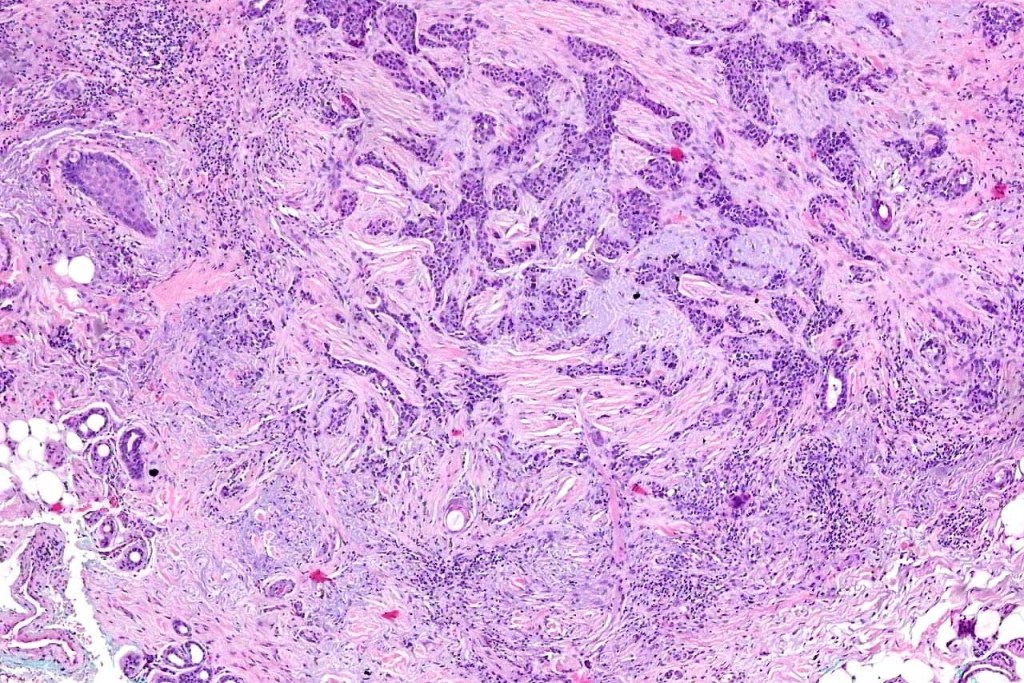

•Widely infiltrating biphasic tumor

•Often extends to the subcutaneous fat

•Perineural infiltration is commonly seen